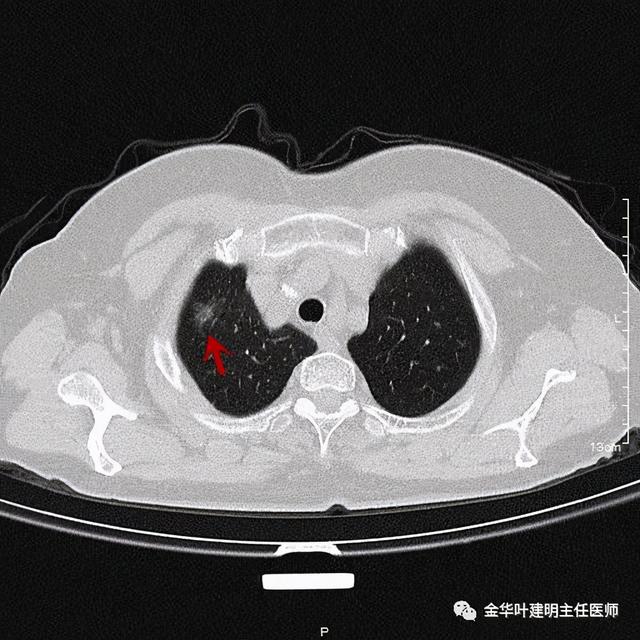

患者为女性 , 今年76岁 , 平时体质甚好 , 家务及地里劳动都胜任 , 头发仍乌黑(我自己倒有一半白发了) 。 肺功能与血气分析正常 。 CT检查图像如下:

可见右肺上叶混合磨玻璃结节 , 有明显分叶征 , 瘤肺边界虽然欠清楚 , 但轮廓比较清晰 。 看着也许会考虑炎性 , 但总觉得其比较僵硬 , 看去不舒服 。 这种病灶一是如果持续存在就极可能是肺癌 , 二是靶扫描显示更清晰的细节 , 如果瘤肺边界还是清楚的 , 也基本是肺癌 。 我们回顾发现其于2019年3月在我们医院做过CT平扫 , 当时报告如下:

靶扫描更清楚显示瘤肺边界较清、分叶及密度不均杂乱 , 并有少许胸膜牵拉凹陷 , 当然考虑是肺癌 , 而且应该是浸润性腺癌了 。 其长径达2.5厘米!靶扫描还发现了平扫没被注意到的另一个病灶: